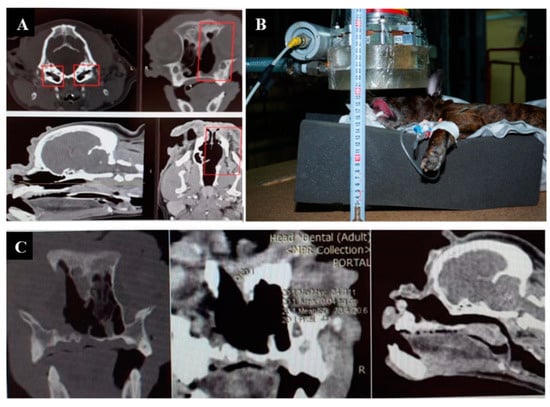

3.1. Case 1

3.2. Case 2

3.3. Case 3

3.4. Case 4

3.5. Case 5

3.6. Case 6

3.7. Case 7

3.8. Case 8

3.9. Case 9